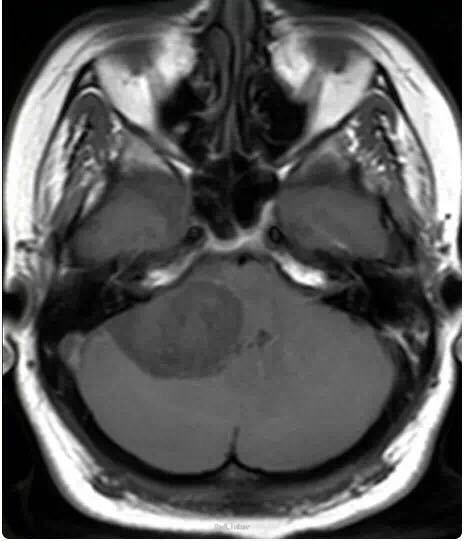

女性患者,34 岁,主因头痛、右耳听力损害以及平衡障碍 3 个月入院。

行头颅影像学检查、轴位 T1 像、轴位增强后 T1 像、冠状位增强后 T1 像以及轴位 T2 像:显示在右侧桥脑小脑角部位有一边界清楚病灶,T1 为低信号,T2 为高信号,并且伴有强化;病灶扩展至右侧颈静脉孔区,导致颈静脉孔增宽,脑干、第四脑室和小脑变形。右侧内耳道正常,病灶无颅外扩展。轴位 T2 加权 GRE 成像显示多发性病灶内出血:

诊断为颈静脉孔区神经鞘瘤。 手术切除辅助以立体定向放疗。